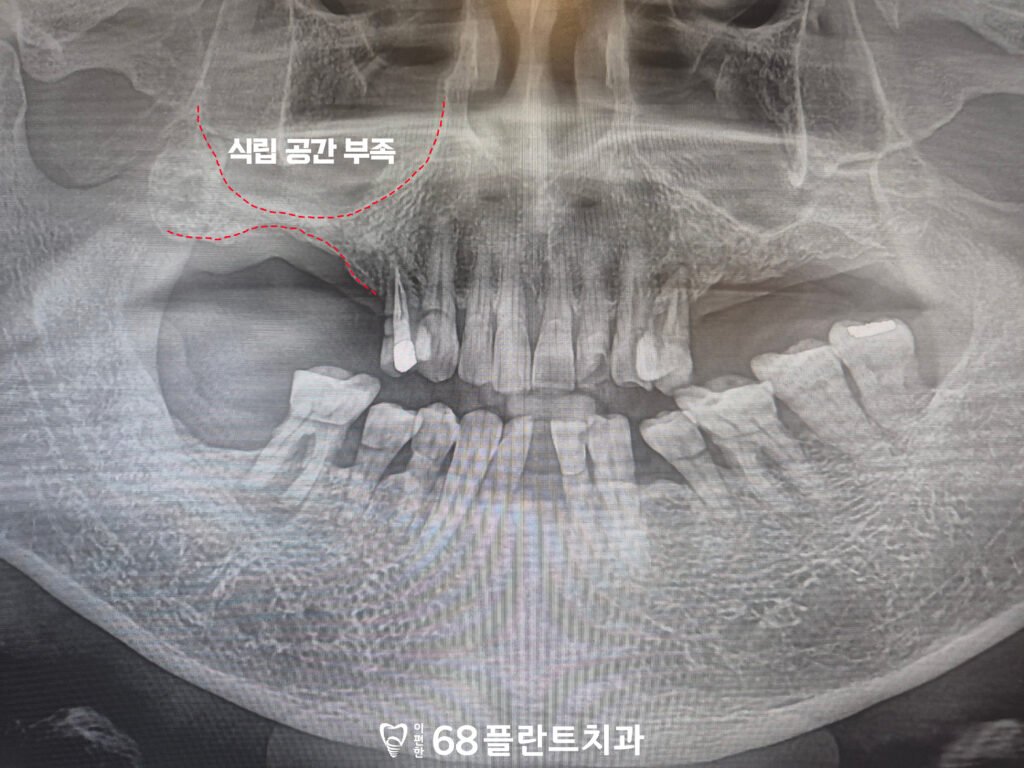

치아의 상실된 시기가 길었다보니

잇몸뼈가 많이 소실되어

식립할 공간이 부족했습니다.

특히 위쪽 어금니 부위에는

상악동이라 불리는 공기 공간이 위치해 있어,

잇몸뼈가 감소할 경우

임플란트를 바로 식립하기가

더욱 어려워질 수 있습니다.

그래서 철산역치과 이편한68플란트에서는

부족한 잇몸뼈를 보완하기 위해

상악동거상술을 먼저 시행한 뒤,

임플란트를 안정적으로 식립하는 방향으로

치료 계획을 수립하였습니다.